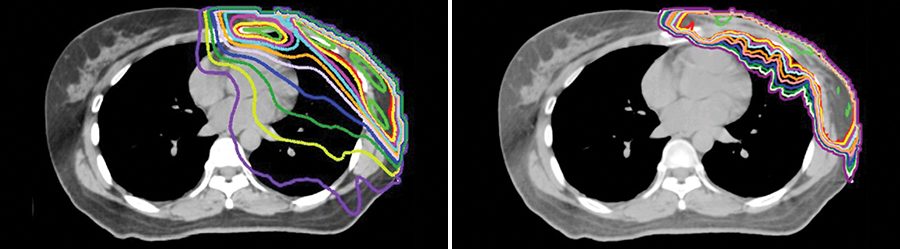

Las modalidades modernas de la radioterapia conformada, como la terapia de protones o la radioterapia de intensidad modulada (IMRT) basada en fotones, contribuyen a garantizar la administración precisa de radiación a los tumores de hígado. En el MD Anderson, el Dr. Koay y el equipo de oncología radiológica gastrointestinal están investigando los beneficios de estos tratamientos para la supervivencia así como sus efectos adversos. La IMRT es la más comúnmente utilizada, pero puede causar daños colaterales al tejido sano del hígado y de otros órganos. Por el contrario, la terapia de protones puede administrar menos radiación al tejido sano que rodea el tumor, lo cual da lugar a menos toxicidad para el hígado y posiblemente a mejores resultados.

Otras innovaciones en cuanto a la radioterapia usada para el cáncer de hígado primario incluyen el refuerzo (o boost) integrado simultáneo con la protección integrada simultánea. Esta técnica administra una dosis de radiación extremadamente alta en el centro del tumor, que suele ser más hipóxico que el tejido tumoral periférico y, por lo tanto, más resistente a dosis de radiación más bajas.

Crane CH, Koay EJ. Solutions that enable ablative radiotherapy for large liver tumors: fractionated dose painting, simultaneous integrated protection, motion management, and computed tomography image guidance. (Soluciones que permiten la radioterapia ablativa para tumores de hígado grandes: painting de dosis fraccionadas, protección integrada simultánea, manejo del movimiento y guía por imágenes de tomografía computarizada). Cancer. 2016;122:1974–1986.